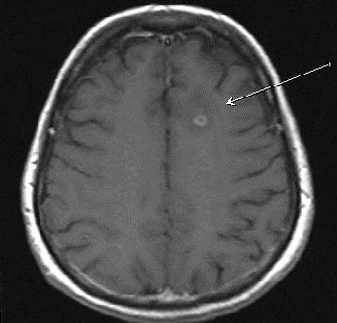

Демиелинизирующие заболевания мозга: МРТ изображения